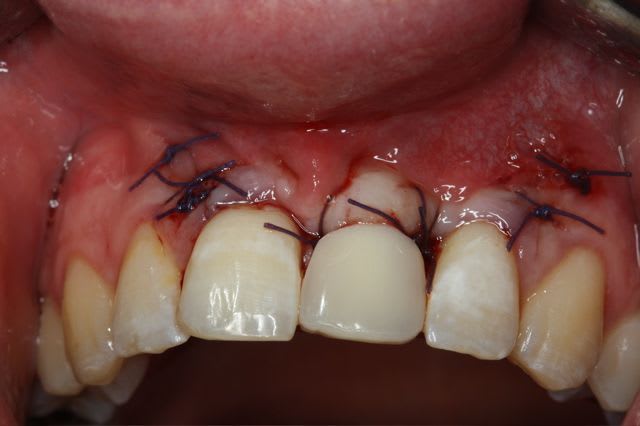

dépose des vis et pose de l'implant à 5mois1/2 avec un cj roulé et mise en place de la vis de cica,

et 3 mois 1/2 après empreinte

15j après essayage pilier et biscuit, visite au labo pour "finition en bouche" et 3 h après scellement.

le liseré visible en cervicale n'est pas le pilier mais le petit suintement dut à la sonde pour enlever les excès de ciment